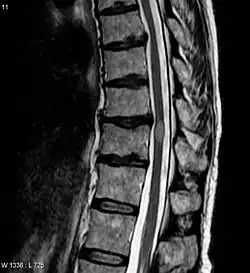

![]() MRI rdzenia kręgowego, widoczne jasne, owalne ognisko poprzecznego zapalenia rdzenia | |

Poprzeczne zapalenie rdzenia (ang. transverse myelitis) – choroba neurologiczna spowodowana zapaleniem w rdzeniu kręgowym[1], które niszczy mielinę, przerywając komunikację między nerwami w rdzeniu a resztą ciała. Często pojawia się po zakażeniu wirusowym.